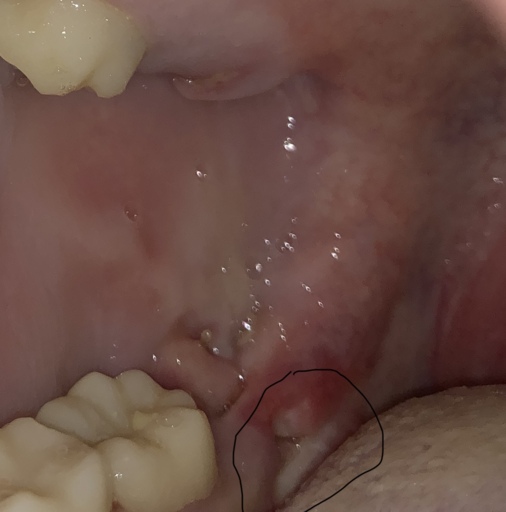

White spot on gum after wisdom teeth extraction

It starts to build up on your teeth after an off-white or yellow color, but it can turn dark in a few circumstances. Tartar can creep below the gumline, and blood from the damaged gums may White spot on gum after wisdom teeth extraction It’s designed to bind to damaged enamel without harming the gums, tongue, or other soft tissues of the mouth. The researchers have already verified the efficacy on teeth extracted from humans